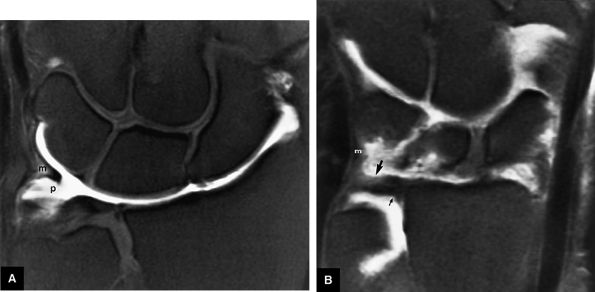

FIGURE 10.73 ● Anatomy of the scapholunate ligament complex on three separate coronal images. (A) Volar component. (B) Membranous component. (C) Dorsal component. (D) On a corresponding axial image all three components of the scapholunate ligament complex are demonstrated. The dorsal scapholunate ligament is horizontally oriented and is perpendicular to the joint. The fibers of the membranous portion of the scapholunate ligament course peripherally and obliquely from the scaphoid downward toward the lunate in a dorsal-to-volar direction. The volar scapholunate ligament courses obliquely from the scaphoid downward to the lunate. This arrangement of scapholunate ligament fibers biomechanically hinges the joint dorsally at the level of the dorsal transverse fibers. In forced extension, scapholunate ligament failure initiates in its volar aspect. S, scaphoid; L, lunate; v, volar component; m, membranous component; d, dorsal component. Arrows correspond to the course of each component of the scapholunate ligament.